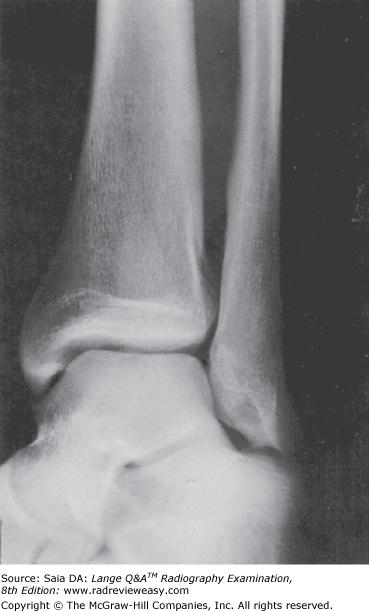

In the AP projection of the ankle, the

B 1 and 2 only

-To demonstrate the ankle joint space to best advantage, the plantar surface of the foot should be vertical in the AP projection of the ankle. Note that the fibula is the more distal of the two long bones of the lower leg and forms the lateral malleolus. The calcaneus is not well visualized in this projection because of superimposition with other tarsals.